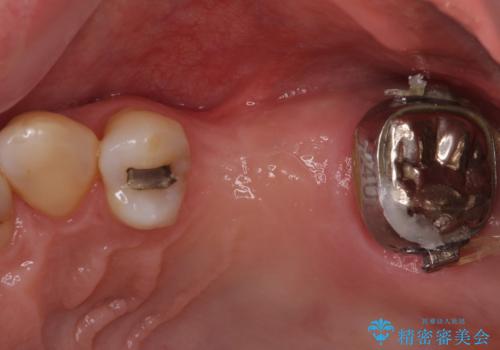

- 奥歯を他院で抜歯した後、インプラント治療を希望とのことで来院された患者様です。

ブリッジの支台を抜歯したことで2本のインプラントが必要であり、その後方はインプラント埋入に必要な骨量が不足していたため、上顎洞粘膜の挙上を行うこととしました。

また、残っている最後方歯は手前に倒れてきていたため、部分矯正により奥に移動させてから、インプラント埋入を行うこととしました。